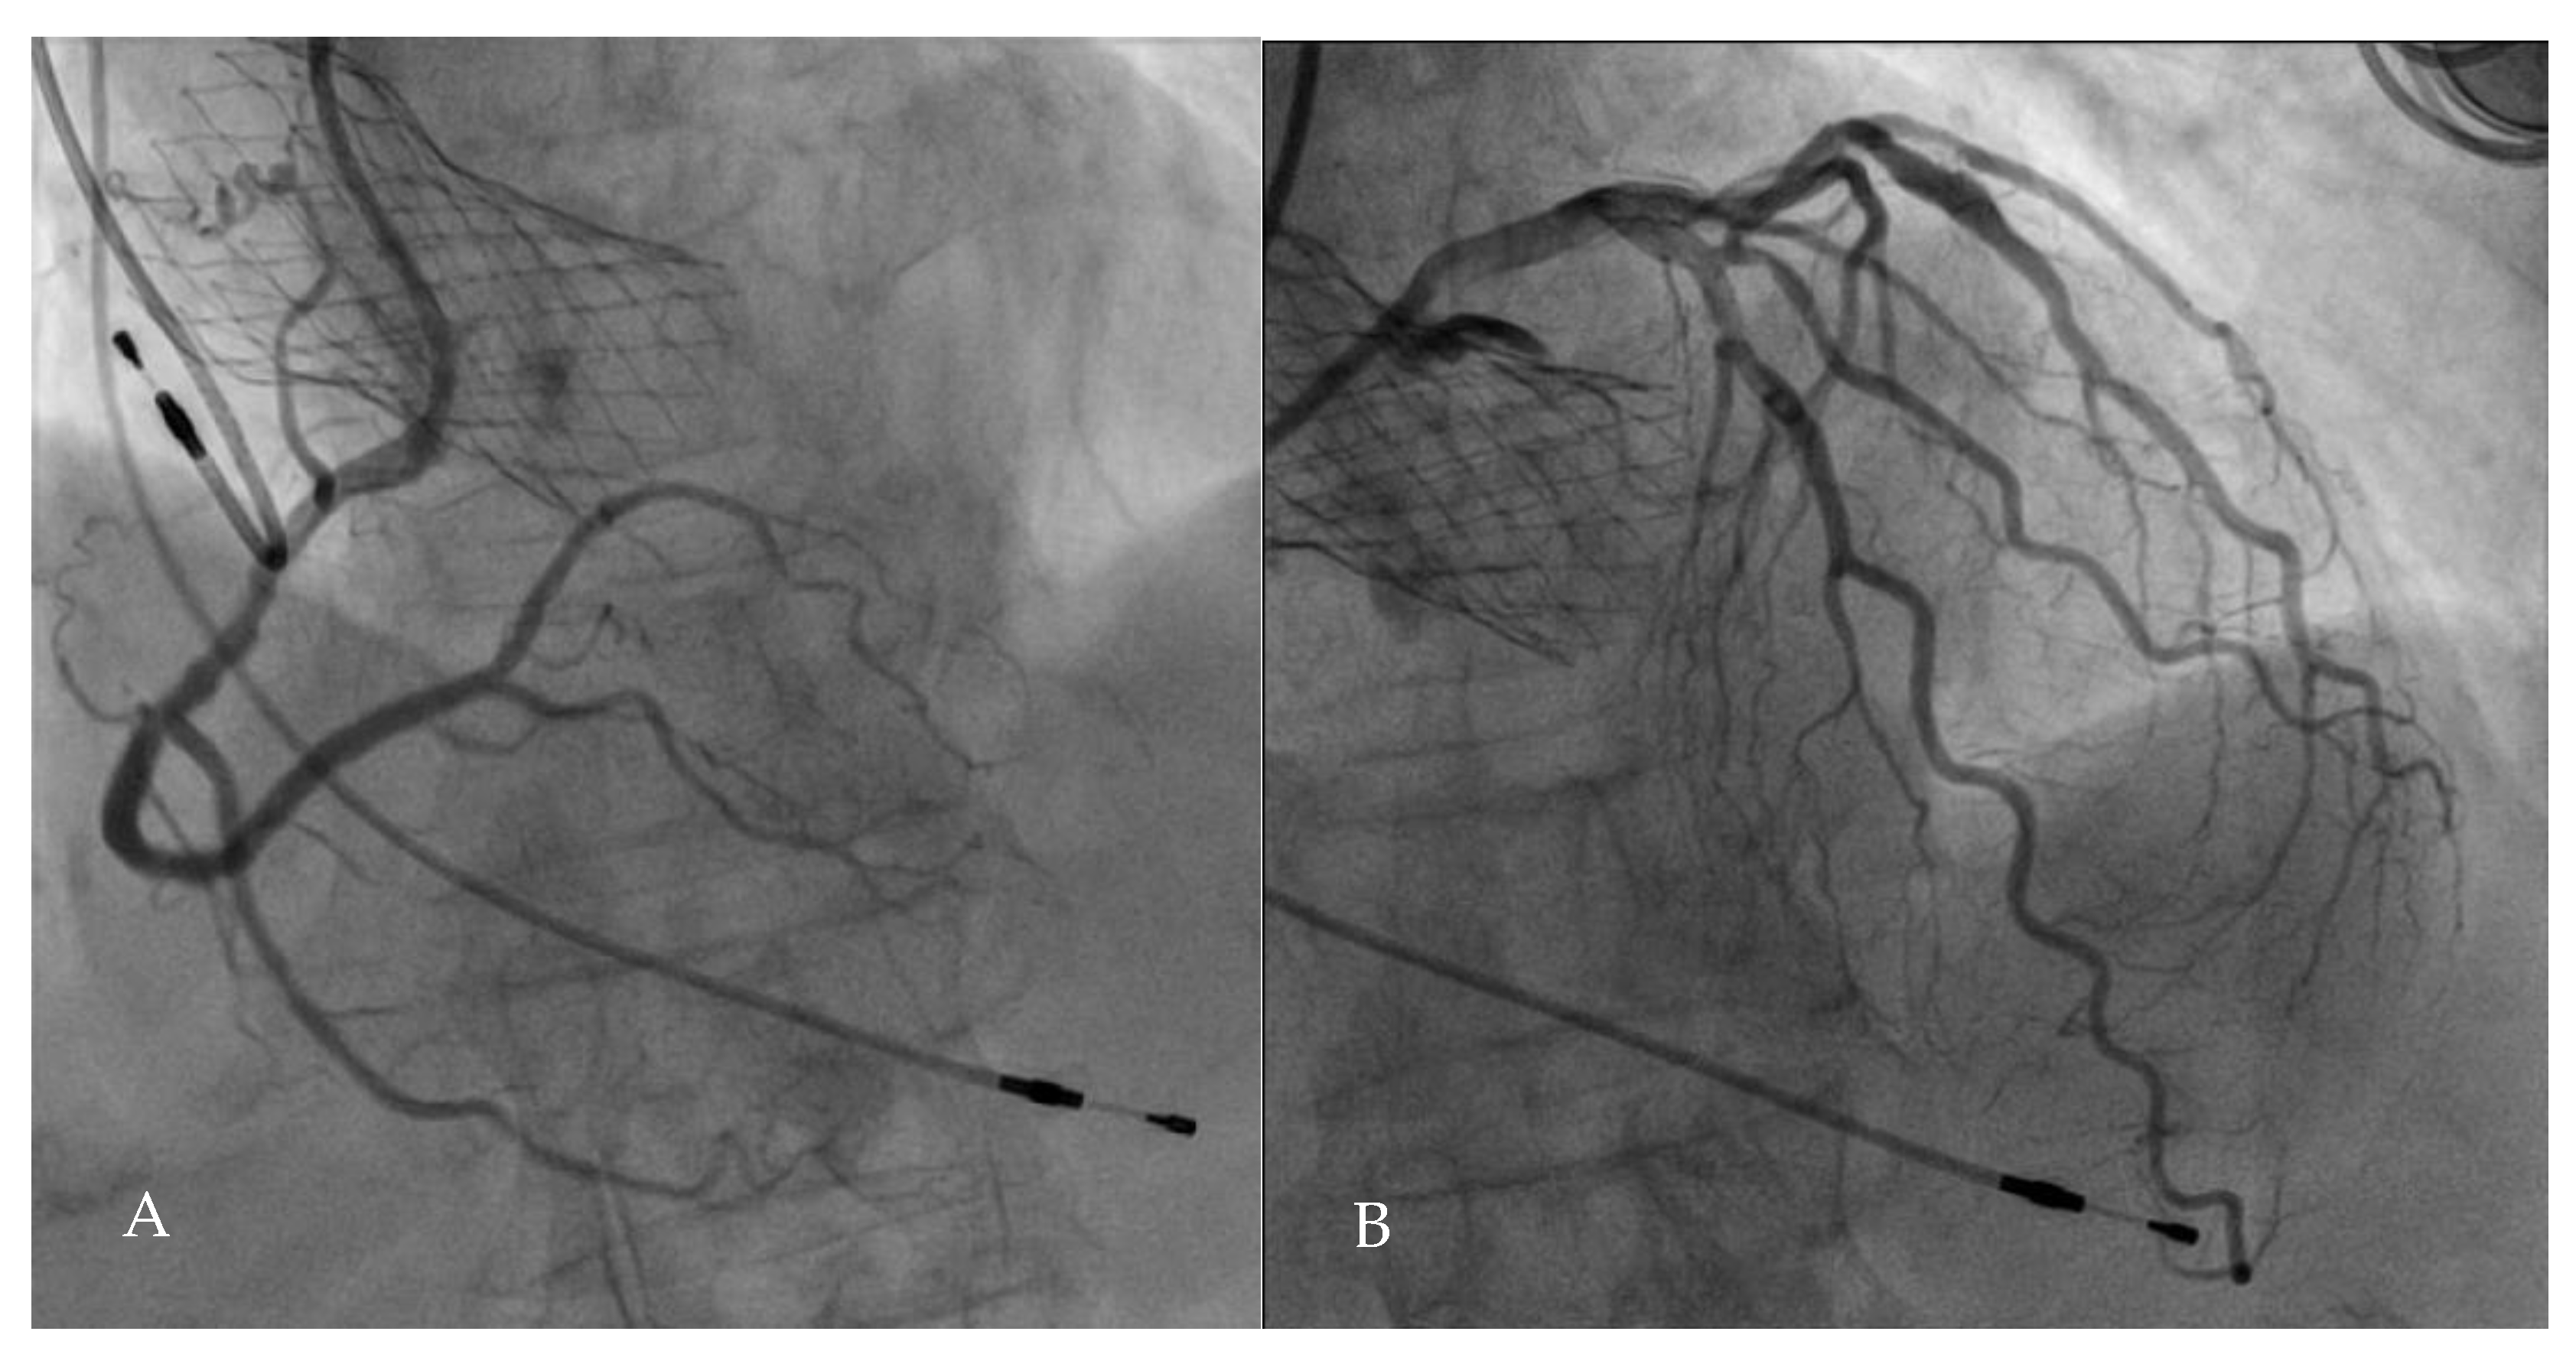

5.1. PCI Upstream to TAVI

5.2. TAVI Upstream to PCI

5.3. PCI and Concomitant TAVI